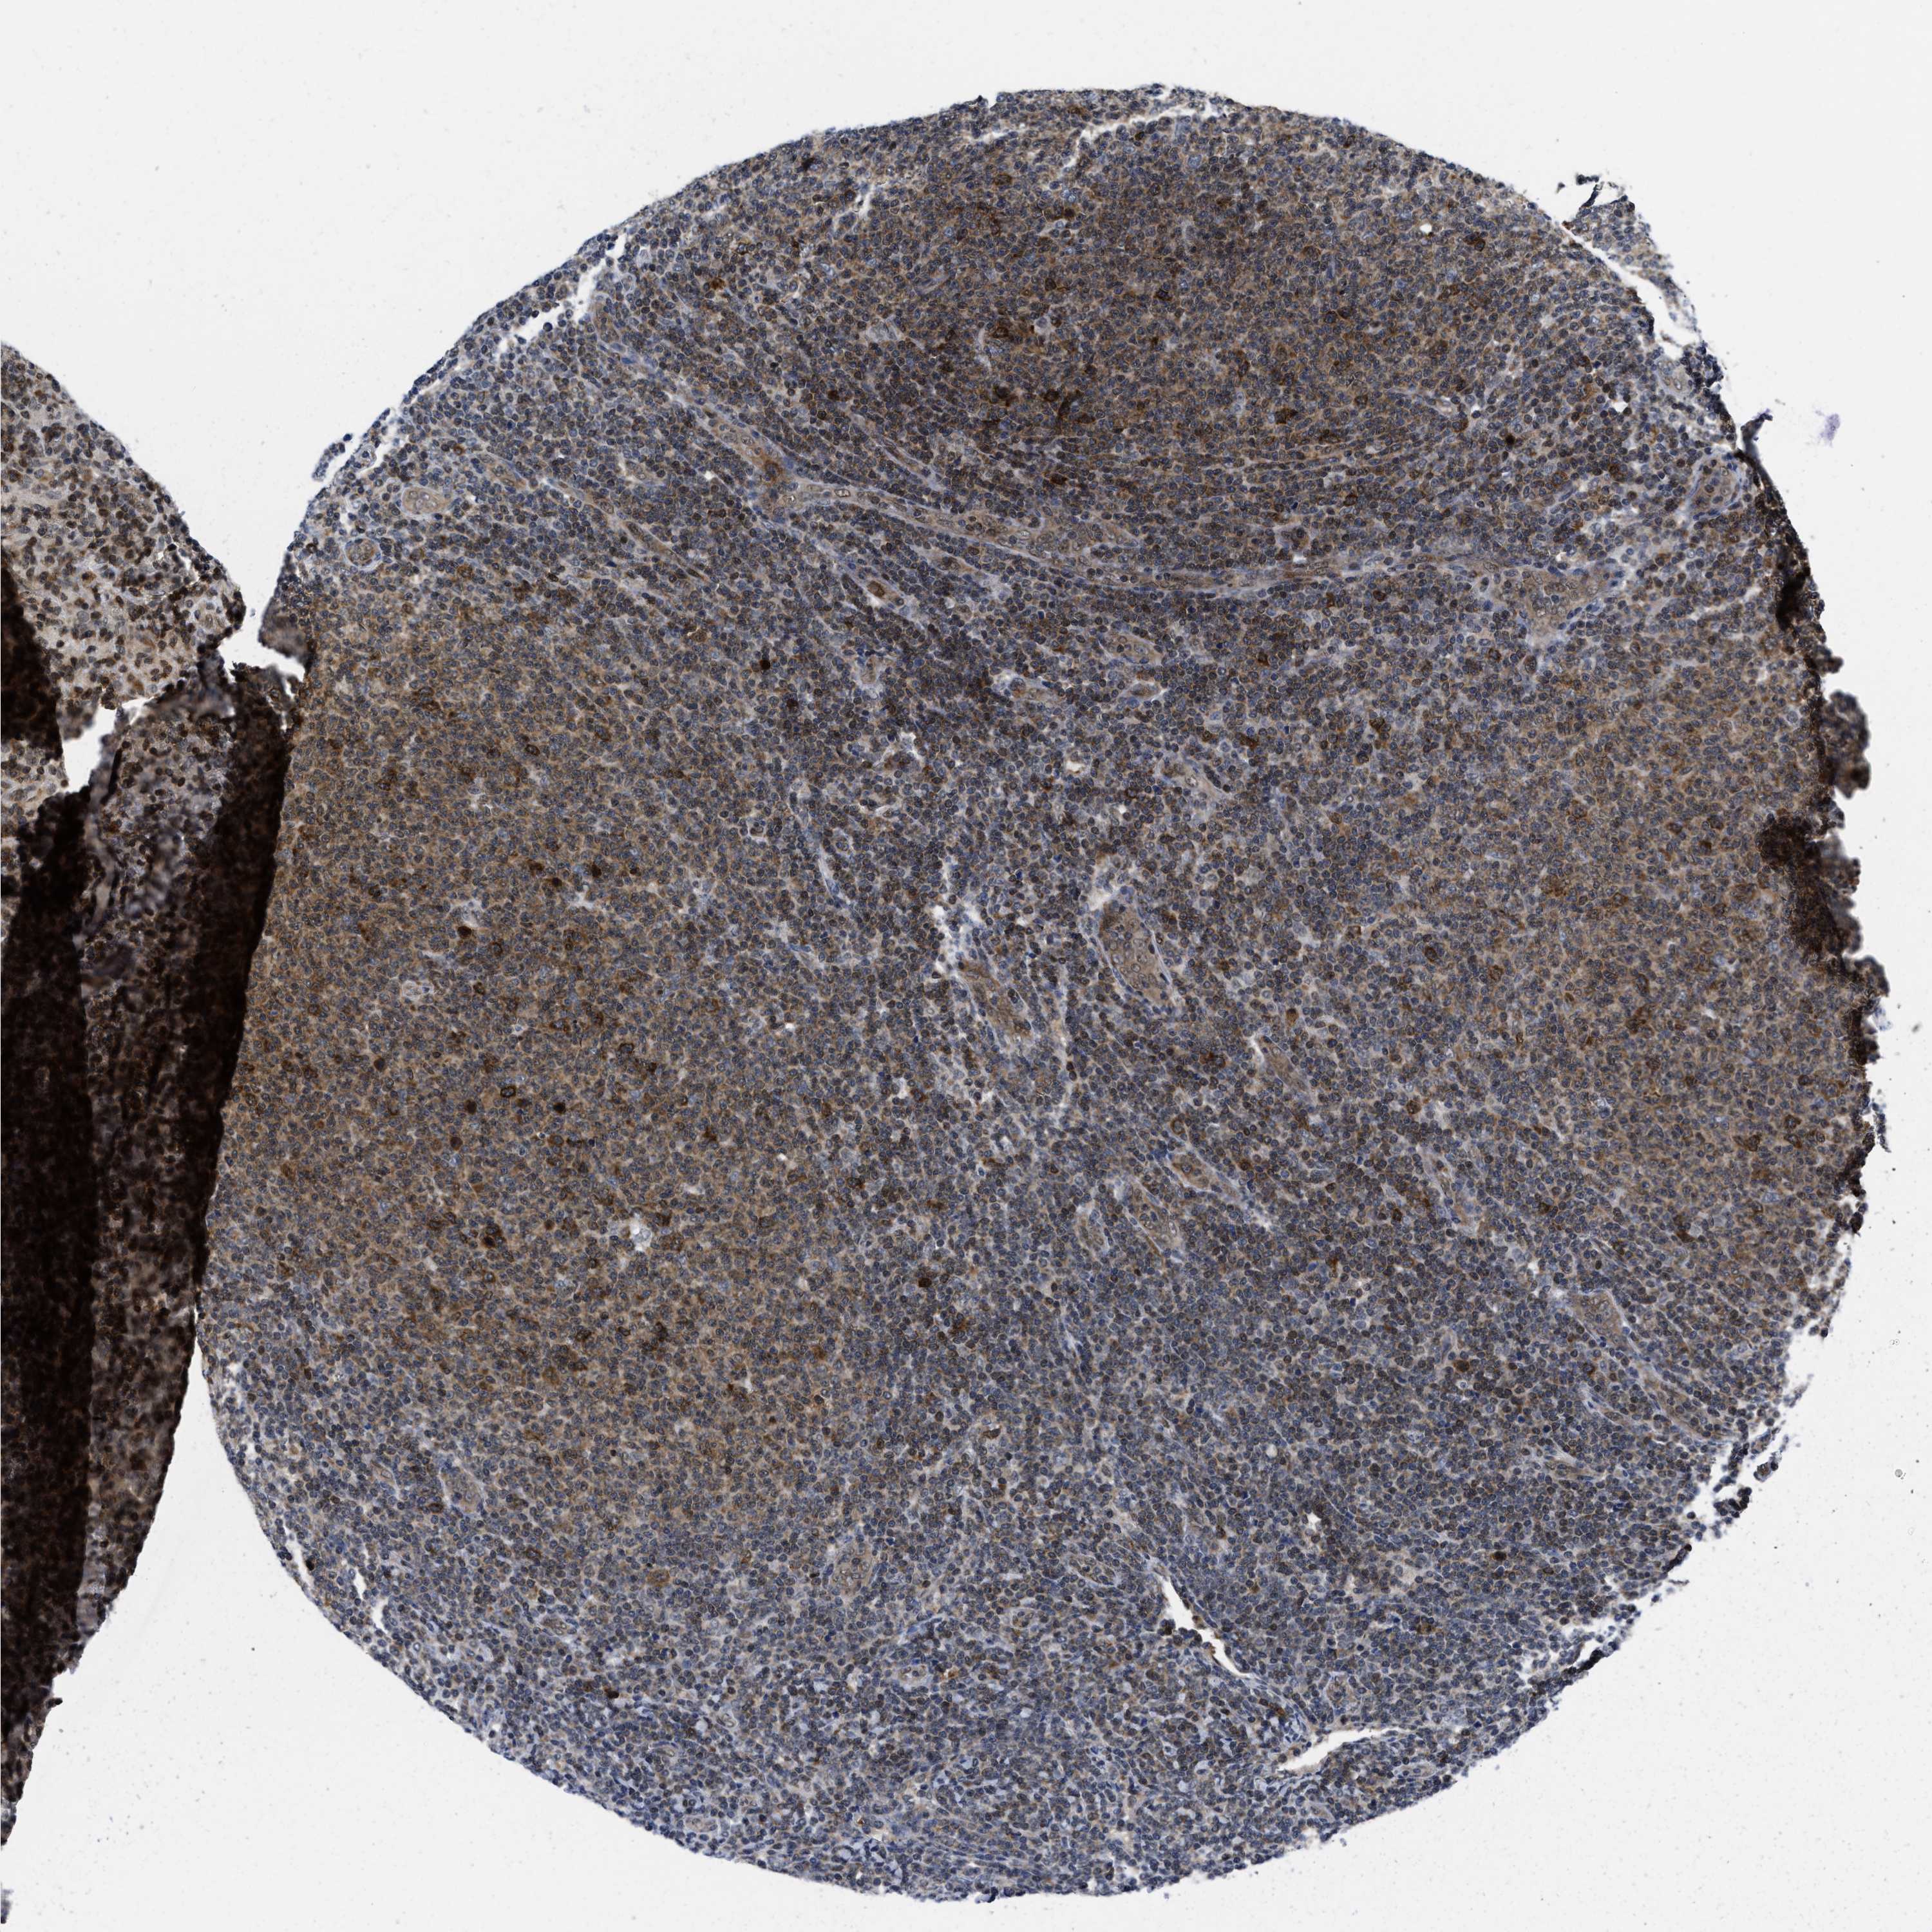

CANCER LYMPHOMA Show tissue menu

LYMPHOMA - Protein expressioni

A mouse-over function shows sample information and annotation data. Click on an image to view it in a full screen mode. Samples can be filtered based on level of antibody staining by selecting one or several of the following categories: high, medium, low and not detected. The assay and annotation is described here.

Each image is clickable and will lead to virtual microscopy that enables deeper exploration of all samples and also displays staining intensity scores, fraction scores and subcellular localization as well as patient and tissue information for each sample.

Antibody HPA001275

Antibody CAB017442

Malignant lymphoma, non-Hodgkin's type, High grade

Hodgkin's disease, NOS

Malignant lymphoma, non-Hodgkin's type, Low grade